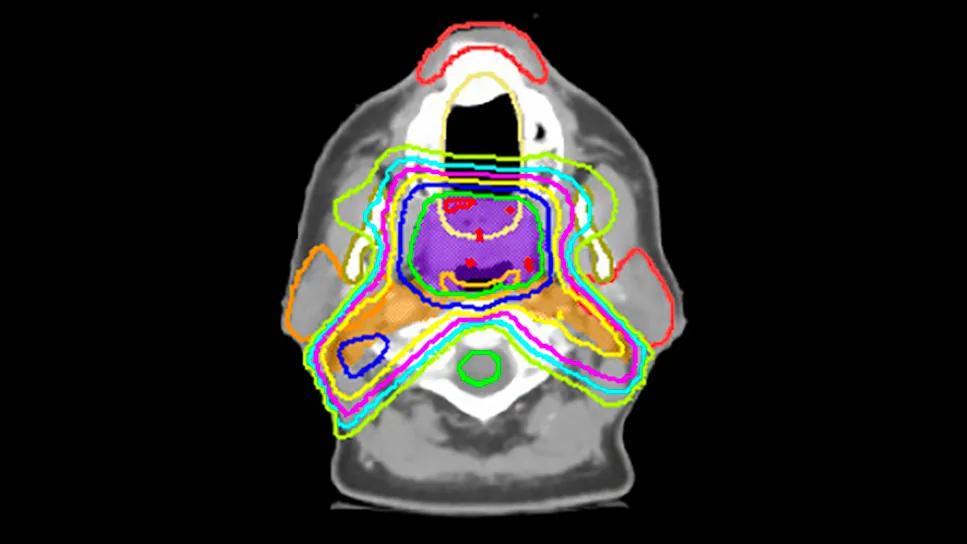

Head & neck image contouring

This approach is especially critical in head and neck cancer, where the anatomy is complex and small variations in contouring can lead to significant differences in dosages to critical structures. Prior studies at other institutions show that 40 percent or more of contours in large networks are modified during peer review, underscoring the challenge.

To evaluate whether these peer review sessions translated into objective improvements, the researchers analyzed dosimetry for oropharynx cancer cases treated with 70 Gy and elective 56 Gy to bilateral necks at three time points: 2018, 2021 and 2024.

In 2018, four of six organs at risk (OARs), although planned in a safe and effective manner, received significantly higher doses when comparing regional plans with HNSS cases. By 2024, only one structure remained significantly different, and median OAR doses at regional campuses improved by 5 to 25 percent compared with 2018.